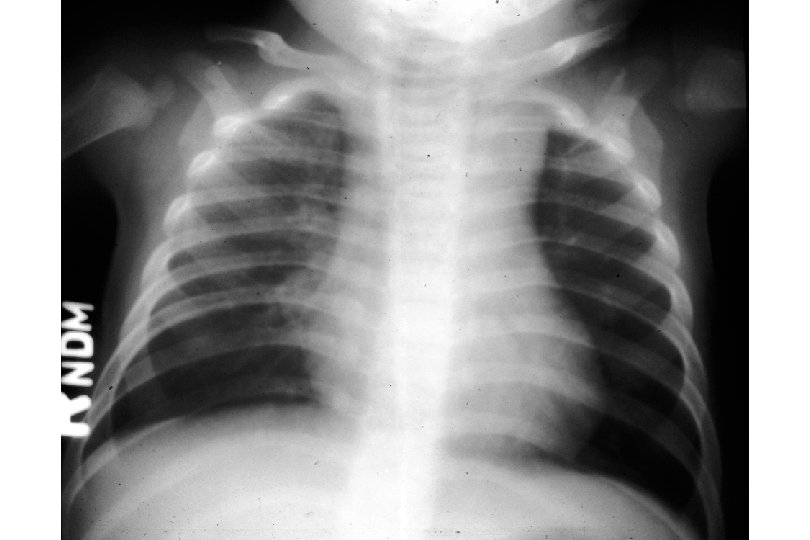

Features of the Pediatric Lower Airway short trachea narrow caliber of all airway structures compliant chest wall horizontal ribs diaphragm as a respiratory muscle